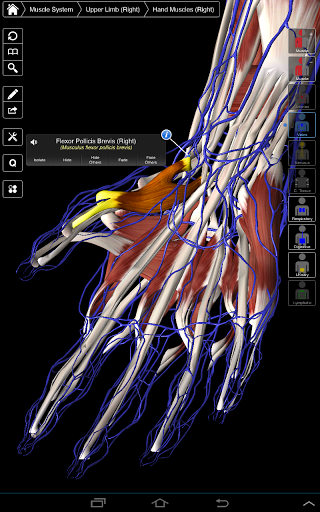

Основна анатомія 3 - це найновіша технологія та новаторський дизайн. Ріжучий 3D-графічний движок, зроблений на замовлення 3D4Medical з усього світу, наділений високоінформативною анатомічною моделлю і забезпечує високу якість графіки, яку не може досягти ніхто інший конкурент.

Програма являє собою унікальний підхід до вивчення загальної анатомії. Графіка не має аналогів і навчається, використовуючи інформативний контент та інноваційні функції, багатий та захоплюючий досвід.

НОВІ 3D-ТЕХНОЛОГІЇ

Основна Анатомія 3 чутлива, візуально приголомшлива і легка. Додаток повністю 3D, що означає, що ви можете переглядати будь-яку анатомічну структуру окремо, а також з будь-якого кута.

Розумна функціональність, знайдена в додатку, дозволяє користувачеві знімати шари м'язів за допомогою інструмента «скальпель». Ця програма надає користувачам можливість увімкнення / вимкнення систем без необхідності скасувати вибір окремих структур або переплутати через безліч попередньо визначених регіональних вкладок, як і інші програми.

---- Більше 4000 дуже детальних анатомічних структур

---- Режим вибору декількох - Сховати / Зменшити / Виділити окремі або кілька структур